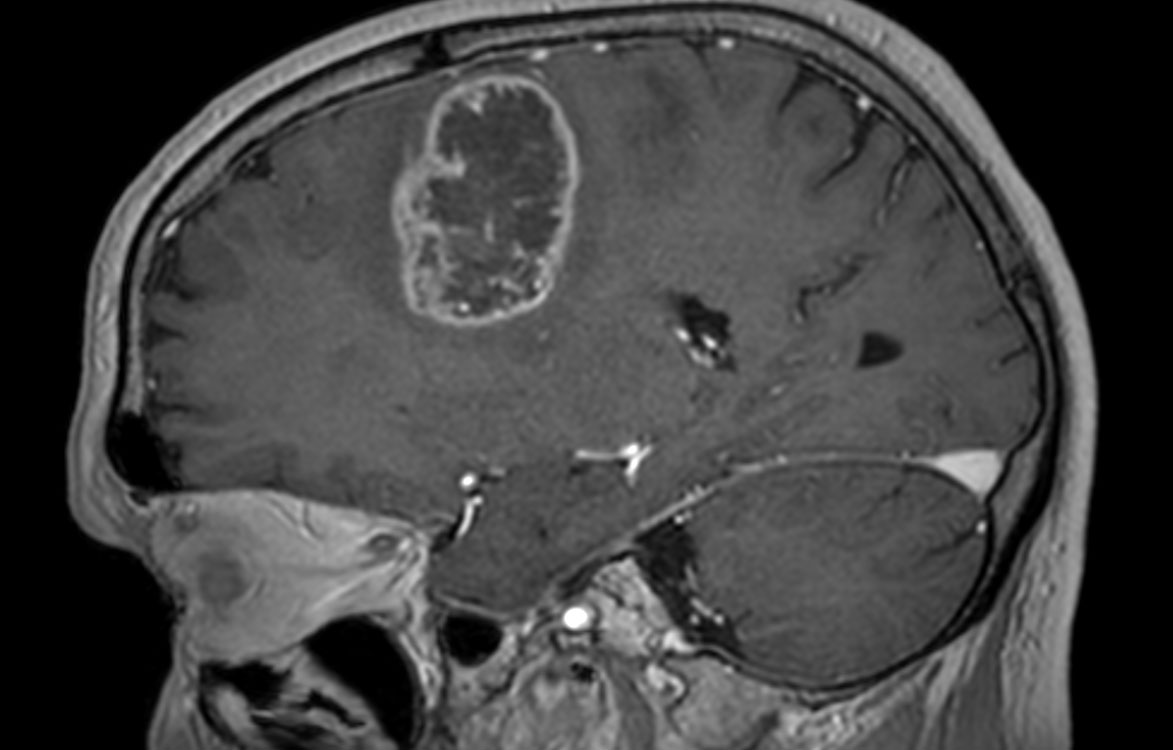

Patient with a revasculerized area with small bleedings. Diagnosed as malignant glioblastoom.

3D T1w TFE (sagittal reformat)

3D T1w TFE with gado (sagittal reformat)